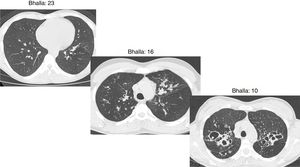

The final result obtained in the modified Bhalla score and in each of the items separately is shown by sex in Table 3. Those for which higher scores were recorded were extension of bronchiectasis, involvement of bronchial generations, and severity of bronchiectasis, thus illustrating practically generalized involvement of the bronchial tree. The modified Bhalla score was 13.70±3.87 points in women and 15.23±3.82 points in men (p=0.024). The items that showed greater involvement in women were sacculations, bronchial generations, and air trapping (Fig. 3).

Fig. 3.

CT images comparison between male and female with the same FEV1: (A) 35 year-old female. Severe bronchiectasis on upper lobes (scored 3), mild peribronchial thickening (scored 1), peripheral mucus plugs are present on upper lobes (scored 2), sacculations are present on left lower lobe. Sparing of distal peripheral zones is detected. Total Bhalla score: 10. FEV1 60%. (B) 40 year-old male. Moderate bronchiectasis (scored 2), mild peribronchial thickening (scored 1), mucus plugging (scored 2) was present on upper lobes. Sparing of distal peripheral zones is detected. Total Bhalla score: 17. FEV1 60%.